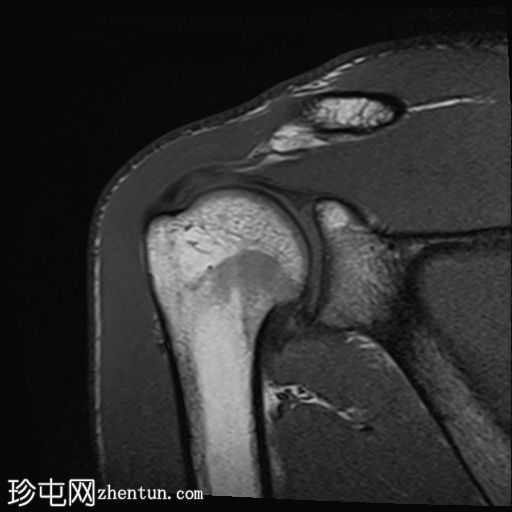

矢状位PD序列

脂肪抑制序列

肱骨头后外侧骨缺损,伴有骨髓挫伤,符合近期肩关节前脱位引起的急性Hill-Sachs损伤。

肩锁关节退行性关节病。